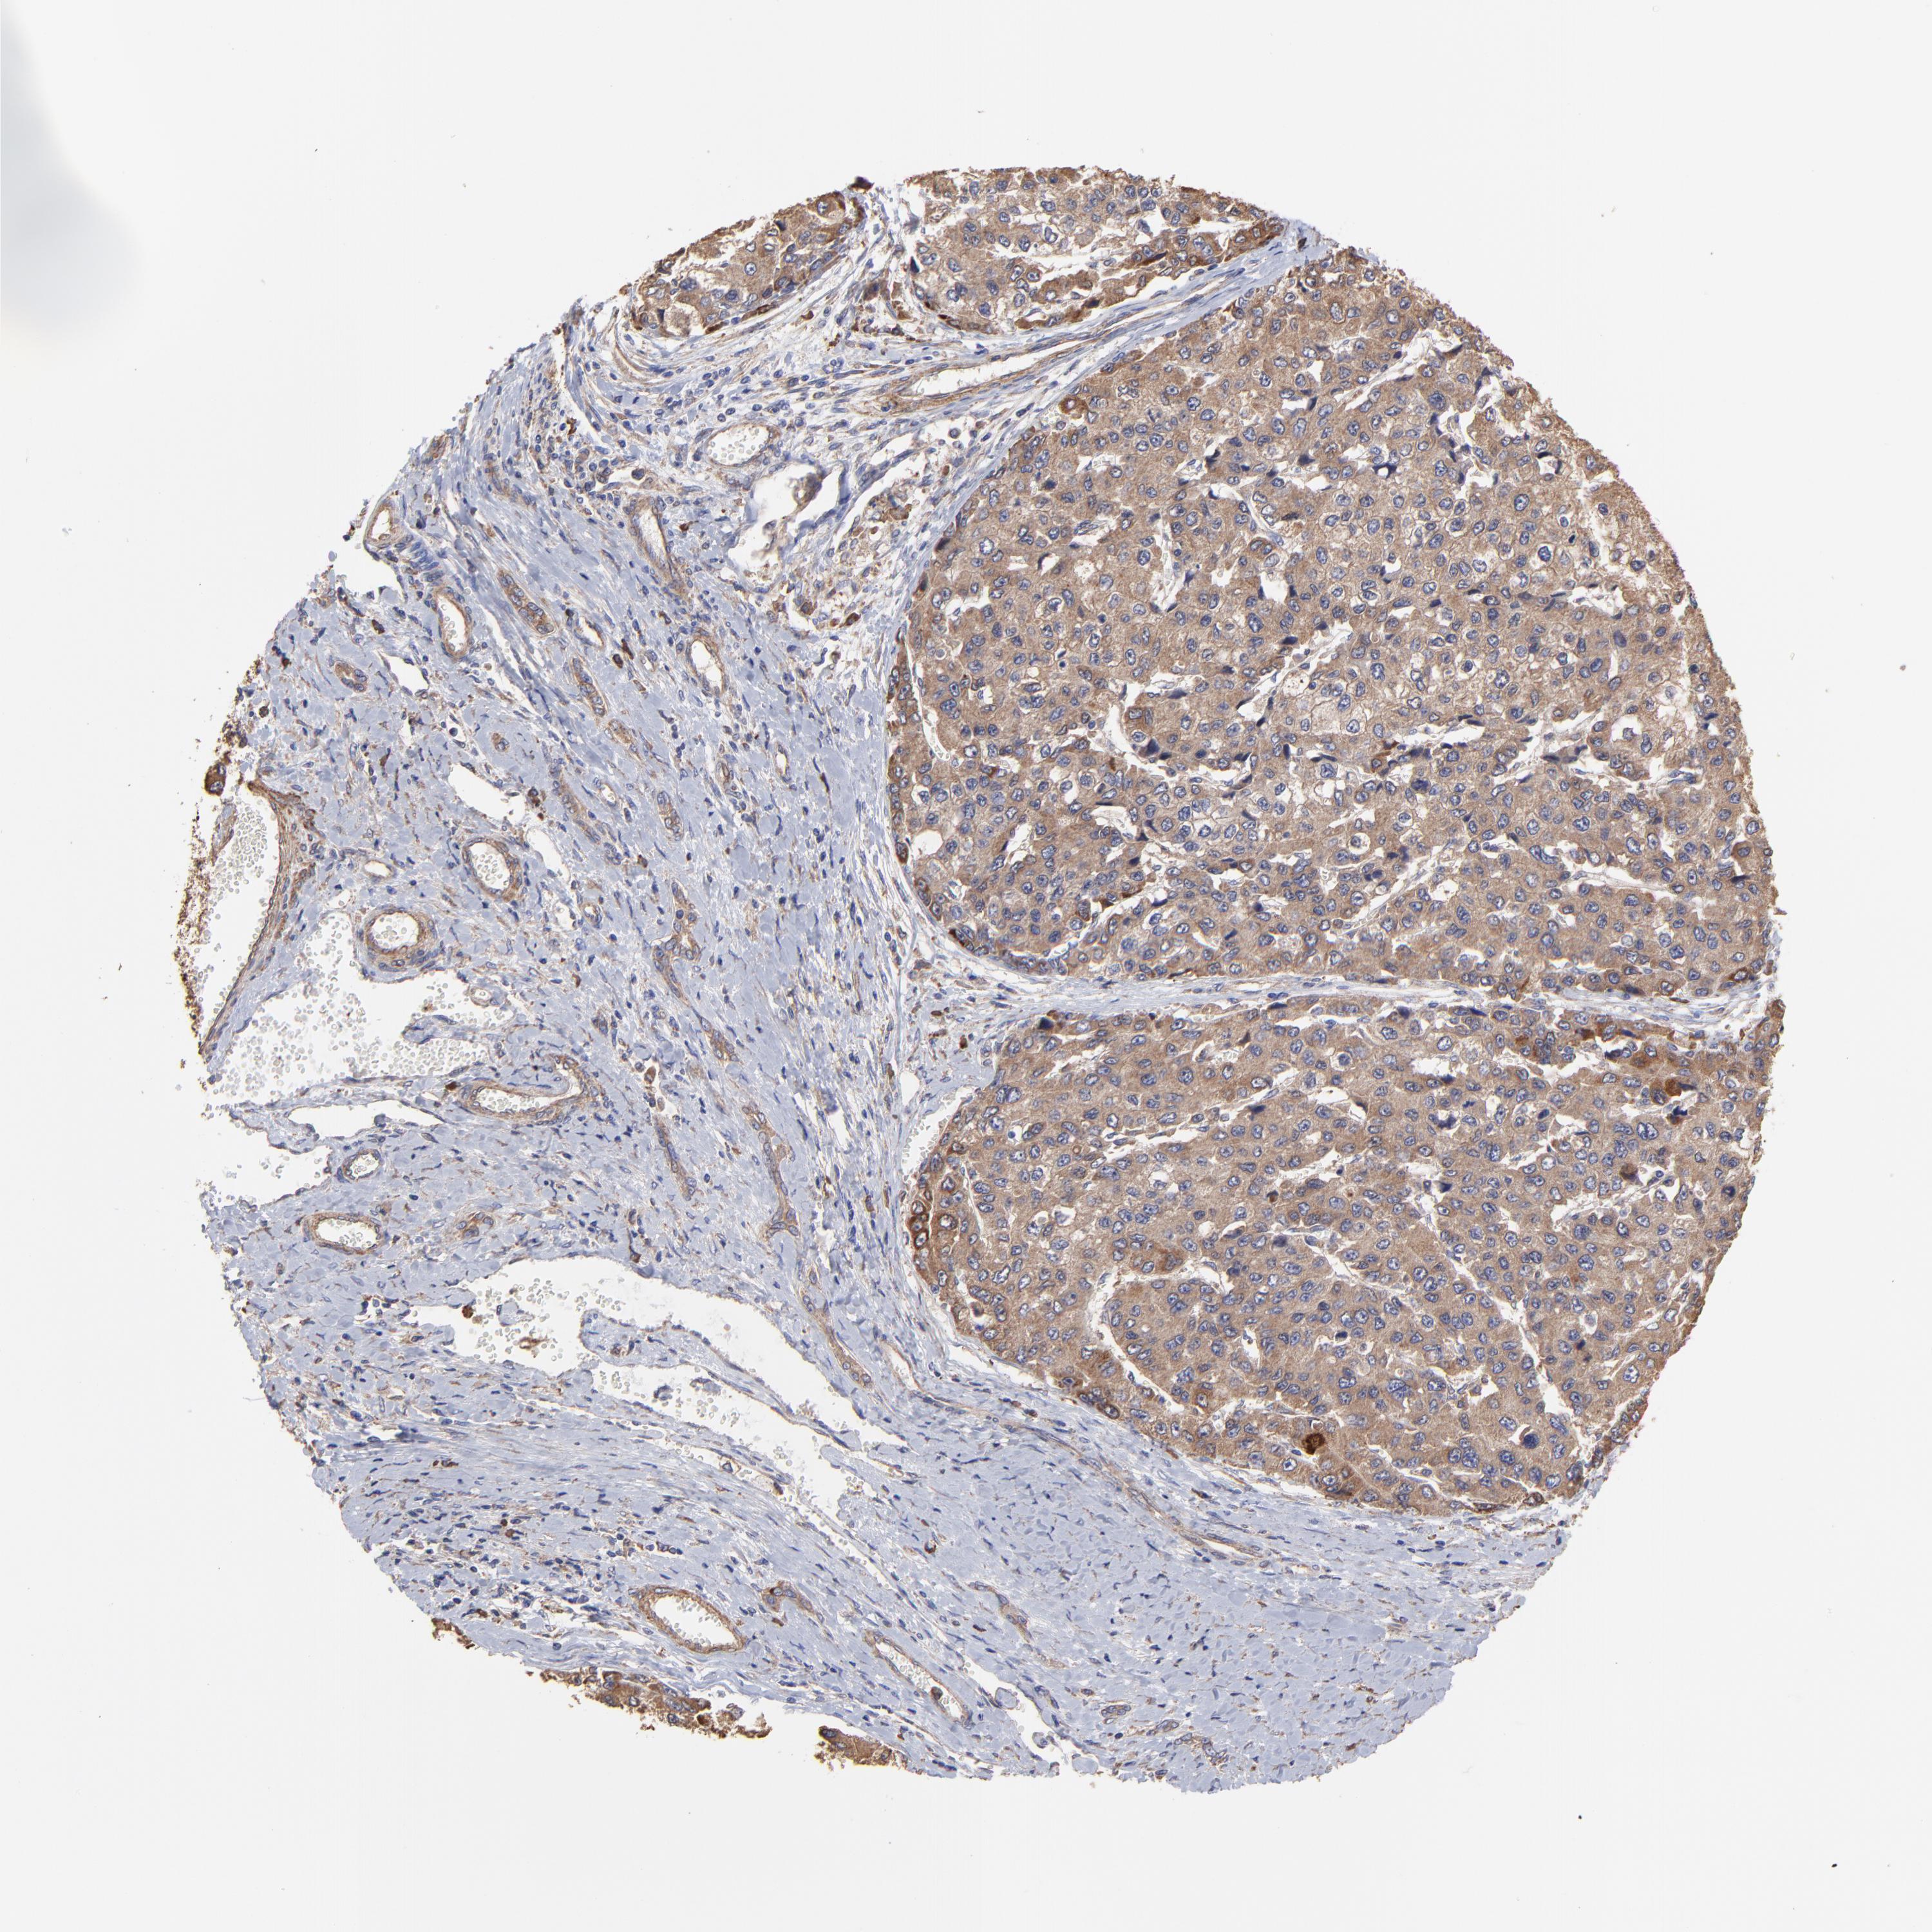

LIVER CANCER - Protein expressioni

A mouse-over function shows sample information and annotation data. Click on an image to view it in a full screen mode. Samples can be filtered based on level of antibody staining by selecting one or several of the following categories: high, medium, low and not detected. The assay and annotation is described here.

Note that samples used for immunohistochemistry by the Human Protein Atlas do not correspond to samples in the TCGA dataset.

Antibody stainingi

Antibody staining in the annotated cell types in the current human tissue is reported as not detected, low, medium, or high, based on conventional immunohistochemistry profiling in selected tissues. This score is based on the combination of the staining intensity and fraction of stained cells.

Each image is clickable and will lead to virtual microscopy that enables deeper exploration of all samples and also displays staining intensity scores, fraction scores and subcellular localization as well as patient and tissue information for each sample.

Antibody HPA002117

Staining

High

Medium

Low

Not detected

Intensity

Strong

Moderate

Weak

Negative

Quantity

>75%

75%-25%

<25%

None

Location

Nuclear

Cytoplasmic/membranous

Cytoplasmic/membranous,nuclear

Carcinoma, Hepatocellular, NOS

Cholangiocarcinoma